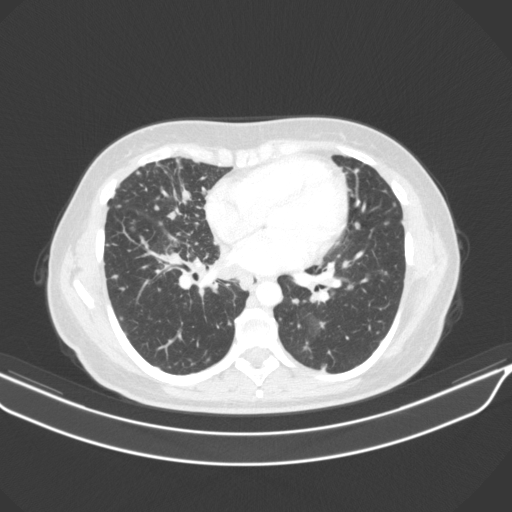

Original VENOUS CT scan

No window - Raw intensity values

Lung window (WL -600, WW 1500 β†’ Low βˆ’1350, High +150)

Mediastinum window (WL 40, WW 400 β†’ Low βˆ’160, High +240)